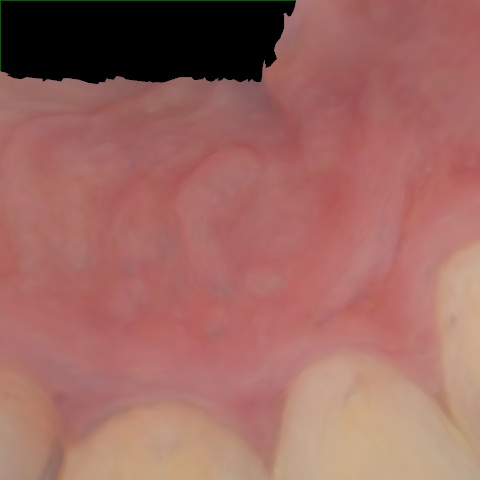

NHD39990

Annotated as "Good"